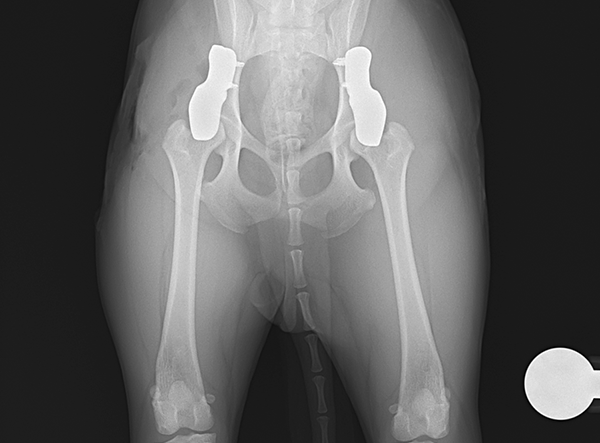

In July 2025, a tiny Shiba Inu weighing only 5.8 kg underwent a pioneering procedure for bilateral hip dysplasia — becoming one of the smallest dogs ever to receive a 3D HIP Implant Implant by Rita Leibinger.

The surgery involved implanting a 2.4 mm 3D HIP Patient-Specific Implant (Titanium) to address severe bilateral hip dysplasia. According to Prof. Dr. Björn Meij (Utrecht University), this miniature Shiba Inu represents the smallest patient on Earth to have successfully undergone this advanced orthopedic procedure. The precision and adaptability of the 3D HIP system allowed for a stable and minimally invasive intervention, tailored to the patient’s unique anatomy.

Post-operatively, the Shiba Inu is progressing well, showing encouraging signs of improved joint stability and mobility. While full rehabilitation will require time and care, the early results are highly promising, resulting in greatly reduced pain and enhanced mobility.